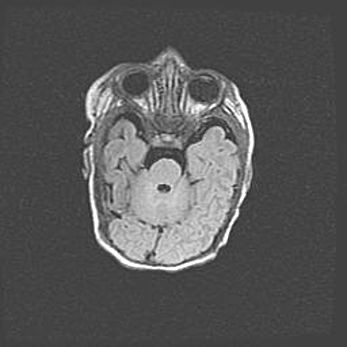

Мальформация Денди-Уокера. Киста задней черепной ямки.

Агенезия мозолистого тела.

Возраст: 2,5 месяца

Вес: 2420 г

Пол: женский

Окружность головы: 37 см

Срок гестации: 32 недели

Мальформация Денди—Уокера — редкий вид патологии ЦНС, представляющий собой врожденный порок развития каудального отдела ствола и червя мозжечка, ведущий к неполному раскрытию срединной (Мажанди) и латеральных (Лушка) апертур IV желудочка мозга. Для этогно синдрома характерна триада симптомов: гипотрофия червя мозжечка и/или полушарий мозжечка, кисты задней черепной ямки, гидроцефалия различной степени. В 70% случаев порок сочетается и с другими аномалиями головного мозга, в частности с агенезией мозолистого тела.